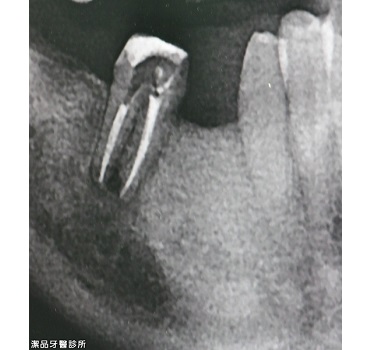

根管重新治療案例-001

案例簡述:

根管重新治療

治療前 嚴重發炎

治療後 (ㄧ年後) 重新根管治療+台大手術一年後可見齒槽骨修復中